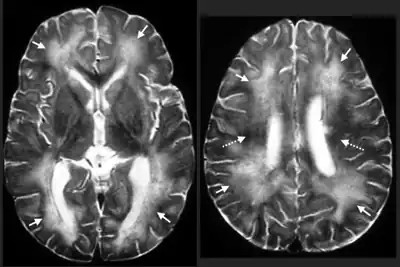

- Eye and brain tissue damage due to the random migration of the larvae.

- Severe neurological signs including imbalance, circling and abnormal behavior, caused by extensive tissue damage due to larval migration through the brain, eventually seizures and coma.

After an animal swallows the eggs, the microscopic larvae hatch in the intestine and invade the intestinal wall. If they are in their definitive host they develop for several weeks, then enter the intestinal lumen, mature, mate, and produce eggs, which are carried out in the fecal stream. If the larvae are in a paratenic host, they break into the bloodstream and enter various organs, particularly the central nervous system. A great deal of damage occurs wherever the larva try to make a home. In response to the attack, the body attempts to destroy it by walling it off or killing it. The larva moves rapidly to escape, seeking out the liver, eyes, spinal cord or brain. Occasionally they can be found in the heart, lungs, and other organs. Eventually the larva dies and is reabsorbed by the body. In very small species such as mice, it might take only one or two larvae in the brain to be fatal. If the larva does not cause significant damage in vital organs, then the victim will show no signs of disease. On the other hand, if it causes behavioral changes by destroying parts of the brain, the host becomes easier prey, bringing the larva into the intestine of a new host.